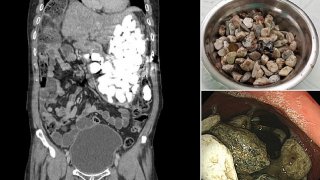

เกือบเอาชีวิตไม่รอด! ชายเกาหลีใต้กลืนก้อนหิน ฝาขวด และเหรียญลงท้อง หวังกำจัดความเครียด

โดย

dusita

(ตอบ 1, 7Y)